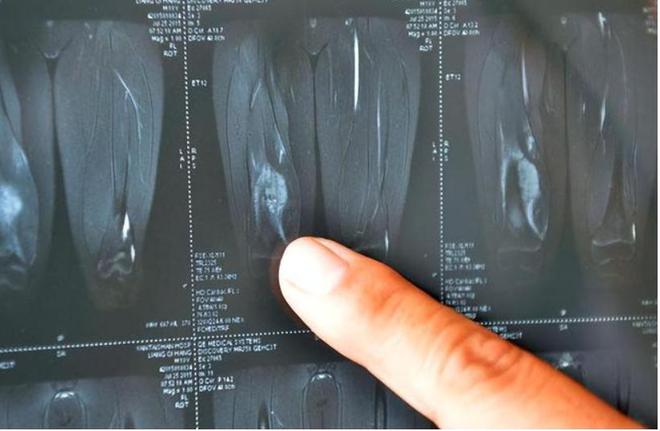

医生告诉她们,治疗的唯一办法就是化疗配合手术,但即使如此,李明馨的生命可能也只剩下五年。

但医生告诉她,情况已经不容乐观,再拖延只会让癌细胞进一步扩散,手术是目前唯一的出路。

终于,手术室的灯熄灭,医生出来告诉她,手术非常成功,癌细胞已经控制住了。